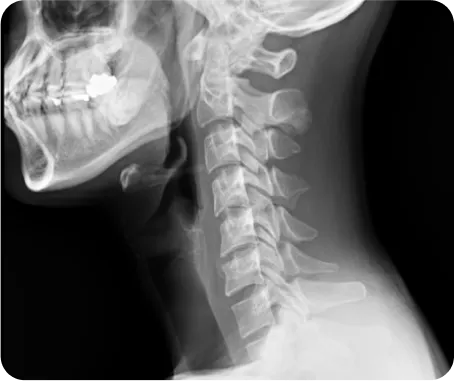

정상목 5kg

목뼈가 받는

하중

일자목 22.2kg

약 4.5배

일자목을 가진 사람이 받는 하중은

정상목의 약 4.5배이기 때문에

교통사고 시 발생하는 충격도

더 크게 발생하게 됩니다.

그래서 일자목인 환자의 교통사고 후유증 치료는

그 방법과 치료 기간이 다를 수밖에 없습니다.

연산당당한방병원은 척추관절을 교정하여

통증을 근본치료 해온 노하우를 담아

엑스레이 검사와 CT, MRI와 같은

영상의학적인 검사를 통해

교통사고 후유증 환자의 체형까지 고려하여

치료가 진행됩니다.